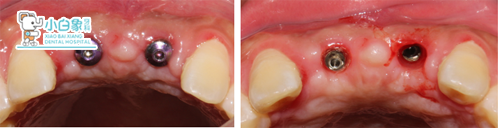

治疗过程:11、21必兰局麻下切开,翻瓣,拔除11后见颊侧骨板缺失,逐级备洞后21植入3.3*10mm,11植入3.3*11.5mm美格真种植体各一枚,植入Bio-oss骨粉,覆盖海奥膜,严密缝合。

局麻后

2017年4月20日 11、21消毒,拆线。

2017年10月15日 11、21必兰局麻下,切开,取出封闭螺丝,测ISQ值:11,近颊、远颊均为75,近舌为60,远舌为56,颊侧为70,舌侧为71,21近颊,近舌、远舌均为77,远颊为76,颊侧、舌侧均为70,上高愈合帽。